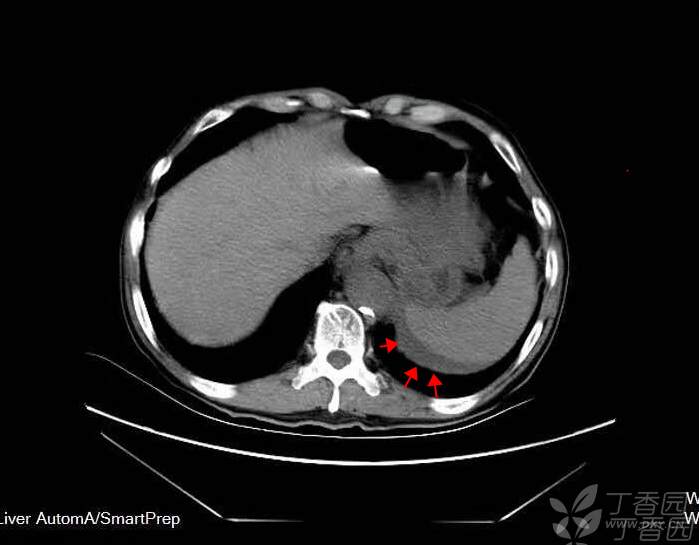

84岁李先生突然感到腹部疼痛难忍,腹部ct平扫显示腹主动脉瘤破裂